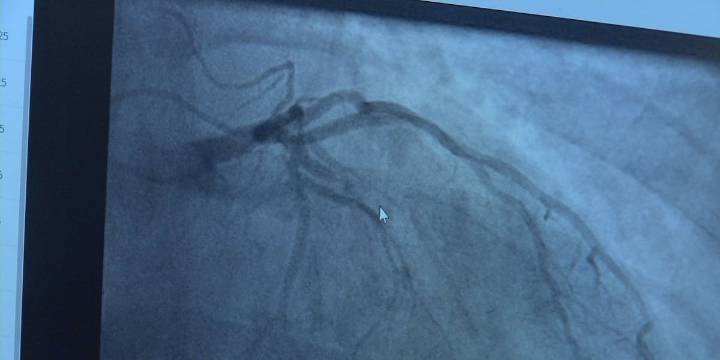

“Some people have what we call silent heart attacks, where you don’t necessarily feel the symptoms of clutching chest pain, making you run to the emergency department. Some people have periods where they just don’t feel that great, and sometimes, they get it misdiagnosed,” said Dr. Uzochukwu Ibe , Interventional Cardiologist at CoxHealth . “Maybe you have a little bit of what we call heart failure, and maybe you have pneumonia and you get antibiotics, and after some testing, we find out it is actually heart disease and heart failure with weakene